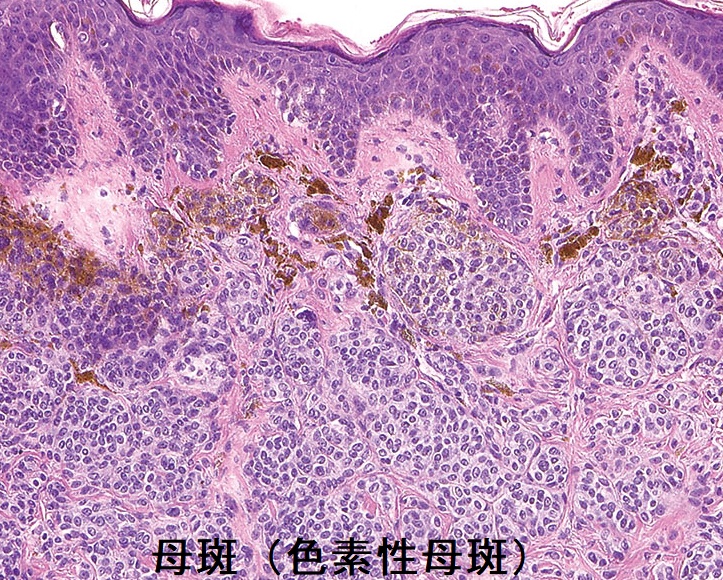

母斑(色素性母斑:pigmented nevus:melanocytic nevus)はメラニン色素を作る良性の黒子(ホクロ)。円形で数mmから20cmを超える巨大色素性母斑まで様々。毛が1-2本生えている事もあります。表面は平坦でスムーズ、わずかな浸潤あり。内部に青白色・青灰色の境界不鮮明な領域あり。

巨大色素性母斑や、急激にサイズ増大するもの、左右非対称形のものは悪性化する可能性があります。

TRα(甲状腺ホルモン受容体アルファ)異常症では、皮膚細胞が過剰増殖状態にあり、主に頭部と頸部に皮膚いぼと母斑(色素性母斑)が生じます。これらの中には、癌化する危険のある遺伝子変異を有しているケースもあります。[Thyroid. 2021 Jul;31(7):1114-1126.]

母斑の数、毎日の紫外線露光量は甲状腺癌、甲状腺結節、甲状腺腫のリスクファクターとされます(Epidemiology. 2017 Sep;28(5):694-702.)。一方で、紫外線暴露により甲状腺癌のリスクが下がるとの報告もあります(Cancer Epidemiol Biomarkers Prev. 2017 May;26(5):684-691.)。